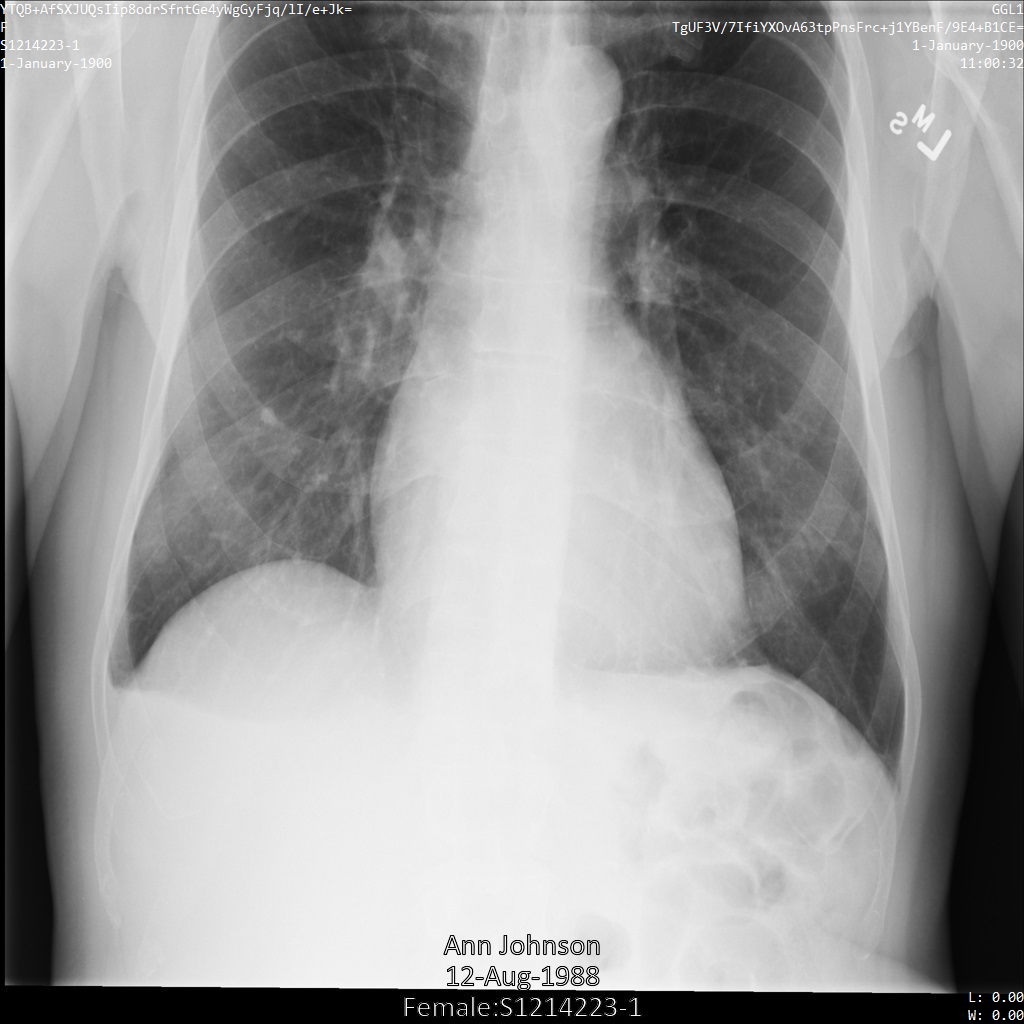

Chacune des sections suivantes fournit des exemples d'anonymisation de données DICOM à l'aide de différentes méthodes. Une sortie de l'image anonymisée est fournie avec chaque échantillon. Chaque exemple utilise l'image d'origine suivante comme entrée :

Vous pouvez comparer l'image de sortie de chaque opération d'anonymisation à cette image d'origine pour voir les effets de l'opération.

L'image suivante montre une radiographie non masquée d'un patient :